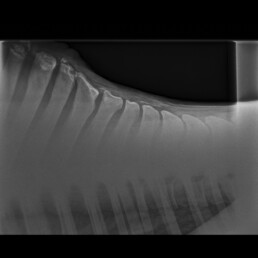

Bildgebende Untersuchung

In der röntgenologischen Untersuchung des Widerristes wurde im Bereich der Tuberositas processus spinosi der Knorpelkappe des T5 ein geringgradig disloziertes Frakturfragment geringer Größe festgestellt (Abb. 6). Ein weiteres Frakturfragment geringer Größe und ohne Dislokation wurde im Bereich der Knorpelkappe des T7 dargestellt. Die Tuberositates processi spinosi der Wirbel T6 und T8 zeigten reaktive Konturveränderungen. In der Unterhaut stellte sich eine Verschattung im Bereich des Narbenzuges dar.

Abb. 5

Frakturfragmente geringer Größe im Bereich der Tuberositates processi spinosi der Knorpelkappen des T5 und T7